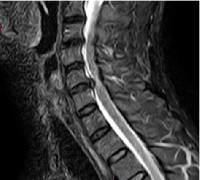

Hernie Discale

Hernie discale "molle"

postérolatérale droite

Coupe IRM

Une hernie discale cervicale qui siège à l’arrière du disque peut aggraver la situation et comprimer soit le nerf sortant entre les deux vertèbres (la racine nerveuse) ou même si la hernie est plus volumineuse, comprimer l’ensemble de la moelle épinière qui passe derrière le disque.

Elle entraîne, lorsque cette compression agit sur le nerf sortant (racine), une douleur sur le bras appelée névralgie cervico brachiale, allant parfois jusqu’aux doigts. Le trajet douloureux renseigne sur le niveau du disque atteint.